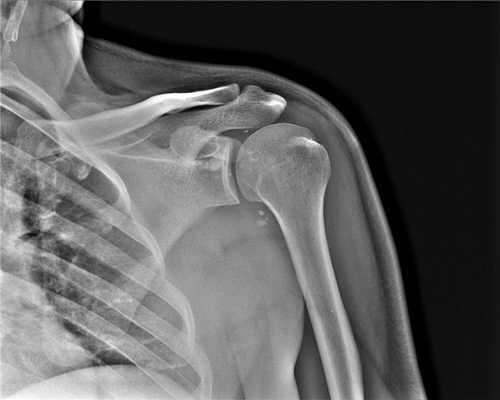

a,b Передний вывих плечевого сустава у женщины 46 лет после падения на вытянутую руку. (а) Рентгенологическое исследование праовго плечевого сустава в прямой проекции с ротацией противоположной стороны туловища на 40° кпереди и на (b) Y-проекция. Суставная впадина пуста. Передненижнее смещение головки плечевой кости ниже клювовидного отростка.

- Рентгенологическое исследование в двух проекциях: прямая тангенциальная (касательная) проекция суставной полости и чрезлопаточная проекция.

Передний вывих: головка плечевой кости расположена кпереди и книзу, обычно ниже клювовидного отростка; в редких случаях она может находиться на нижней границе суставной полости.

Задний вывих: головка плечевой кости перекрывает границу суставной полости; суставная щель не визуализируется.